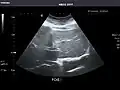

Spleen -

Spleen: Normal in size.